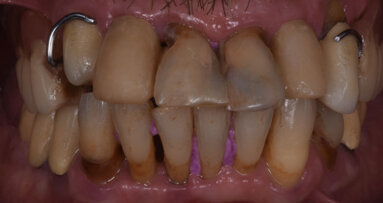

Nell’autunno 2009 una paziente di sesso femminile e di 37 anni si era riferita presso il nostro studio per migliorare il proprio sorriso (Fig. 1). All’epoca la paziente venne trattata con un DSD (Digital Smile Design) che prevedeva un allungamento di corona clinica sugli incisivi superiori, l’inserzione di un impianto nel sito 22, una GBR e innesto di connettivo per migliorare il profilo emergente del dente stesso e la riabilitazione con corone singole (Figg. 2, 3).

Le radiografie del caso completato nell’inizio del 2010 (Fig. 4) evidenziano la precisione del lavoro che è poi stato mantenuto nel corso degli anni. L’incisivo centrale destro 11 era stato trattato con apicectomia in passato ed era l’unico dente non vitale della riabilitazione. La paziente era seguita dal protesista che aveva portato a termine il caso. Nel 2021 la signora si è ripresentata con sintomatologia sul dente 21. Il lavoro eseguito nel 2010 era ancora in buone condizioni fatta eccezione per 11-12 ove 12 presentava una recessione gengivale con esposizione del collarino della cappetta galvanica che supportava la corona in ceramica e 11 presentava una piccola fistola nella sua porzione vestibolo distale (Figg. 5-7). La diagnosi era abbastanza semplice, l’11 aveva una frattura verticale e una prognosi infausta.